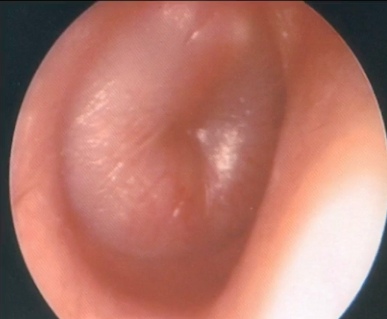

Q

A

Otitis seromucosa

How well did you know this?